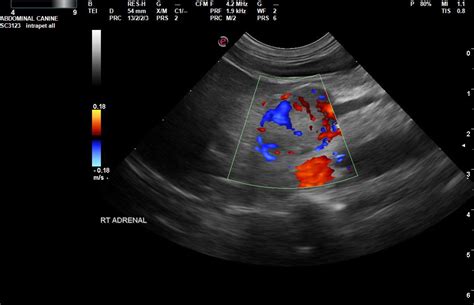

Imaging Studies

To determine the physical characteristics of the mass, the following imaging studies may be used:

- CT Scan (Computed Tomography): Often the first-line imaging modality to assess the size and appearance of the mass.

- MRI (Magnetic Resonance Imaging): Provides detailed information about the tissue composition to help distinguish between benign and malignant tumors.